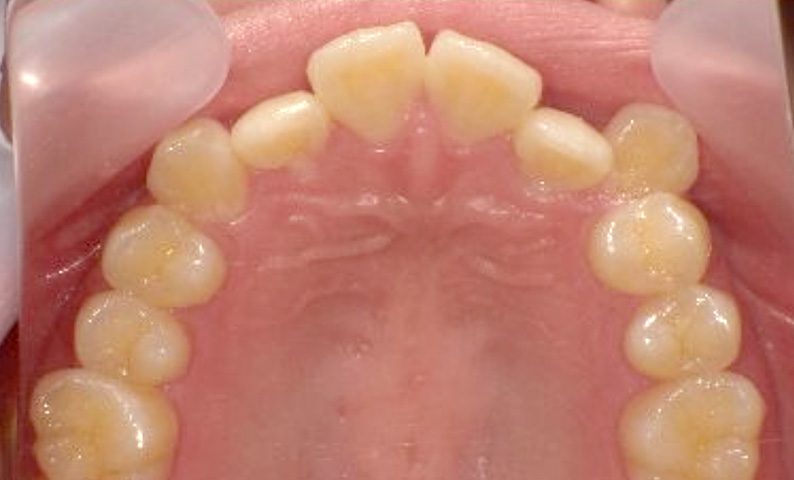

症例_002 上下顎の部分矯正

治療期間:7ヶ月金額:54万円+税女性前歯のガタガタ出っ歯八重歯

| Before | After |

|---|---|

|